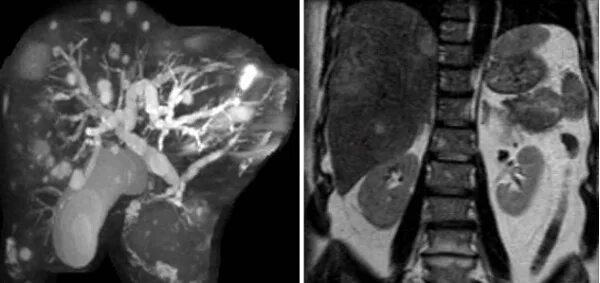

Подготовка к мрт печени